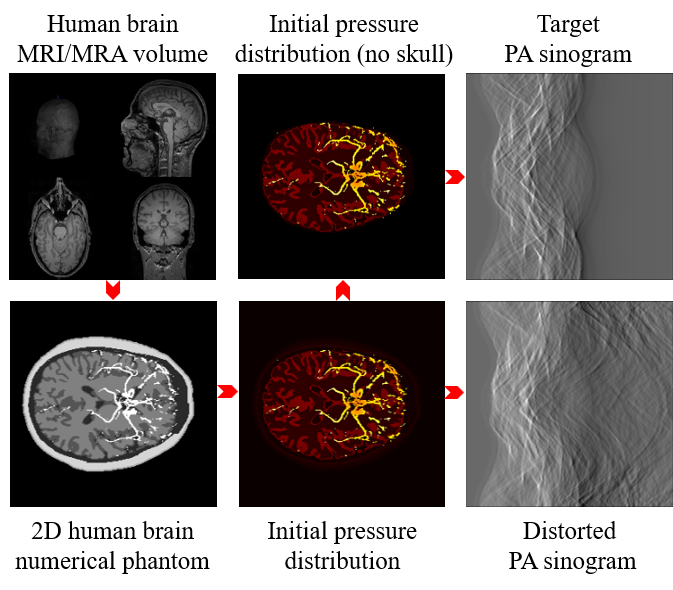

Figure 4: The preparation process of PA digital brain dataset[10].

This dataset has a rigorous preparation process. Firstly, T1-weighted 3D MRA images from the IXI dataset from Hammersmith Hospital were used to generate a 2D numerical model of the human brain. By superimposing the six types of tissue of the scalp, skull, vessel, gray matter, white matter, and cerebrospinal fluid, it can generate a pseudo-3D human brain numerical model size of 12×256×25612\times 256\times 256. More specifically, from top to bottom, it consists of two layers of scalp, five layers of scalp and skull mixture layer, four layers of scalp, skull, and cerebrospinal fluid mixture layer, and one layer of all six types of tissue mixture layer mentioned above. Then, the optical simulation of the human brain numerical model was carried out by MCXLAB[23], obtaining corresponding optical fluence. The initial pressure distribution is obtained by multiplying the optical flux with the corresponding optical absorption coefficient. Finally, the initial pressure distribution and its removal of skull and scalp tissue were respectively imported into the k-Wave toolbox for acoustic simulation[24], generating distorted signal and target signal. The whole data preparation process is shown in Fig.4.